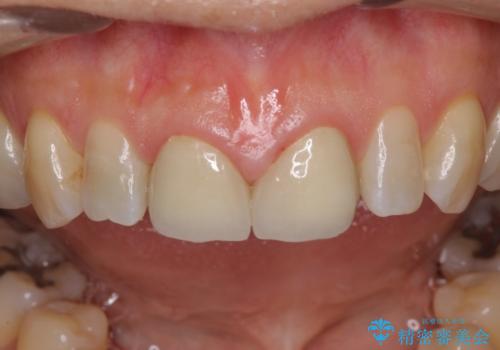

前歯のすきっぱ&奥歯の虫歯 セラミッククラウンで徹底的に治す

咬み合わせや元のご自身の歯の色に特徴があったため、セラミッククラウンを修正したり、隣の歯を金属を外して白いつめものに変えたりして経過観察を長めに行いました。

患者様には大変満足して頂きました。

セラミッククラウンですき間を埋める場合、矯正治療と比較して、早い、本数によっては安価というメリットがあります。デメリットとしてはわざと大きい形態にするので、角度が急になる場所が掃除しにくい、ご自身の歯を削る等があります。